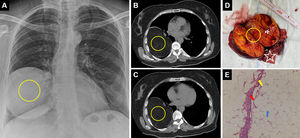

Posteroanterior chest radiograph (A) and thorax computed tomography axial sections (B, C) show a 110mm×105mm×100mm, well-circumscribed, intraparenchymal lesion with fat density in the right lower lobe (circle). Macroscopic structure of lung tissue (D) after lower lobectomy and angiofibrolipoma (circle) and lung tissue (asterisk) after excision of the intraparenchymal lesion are shown. A benign mesenchymal neoplasm comprising mature adipocytes (blue arrow), capillary vascular vessels (red arrow) and fibrocytes (yellow arrow), separated from the lung by a smooth fibrous capsule, is observed in the lung neighborhood (E).